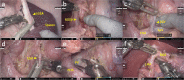

Methods: First, the suturing time in the dry model was measured in the virtual telesurgery setting to determine the latency time threshold. Second, a surgeon cockpit and a patient unit were installed at Okazaki Medical Center and Fujita Health University, respectively (approximately 30 km apart), and connected using a 10-Gbps leased optic-fiber network. After evaluating the feasibility in the dry gastrectomy model, robotic distal gastrectomies with D2 lymphadenectomy and intracorporeal B-I anastomosis were performed in two porcine models.

Results: The virtual telesurgery study identified a latency time threshold of 125 ms. In the actual telesurgery setting, the latency time was 27 ms, including a 2-ms telecommunication network delay and a 25-ms local information process delay. After verifying the feasibility of the operative procedures using a gastrectomy model, two telesurgical gastrectomies were successfully completed without any unexpected events. No fluctuation was observed across the actual telesurgeries.